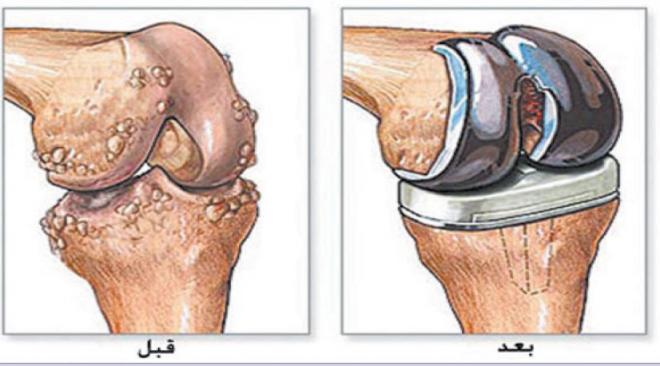

Hip fracture surgery is one of the treatment options available for those who have experienced a hip fracture. This procedure can be somewhat challenging, as it sometimes involves making an incision in the skin around the hip area to realign the broken bones. Despite the seriousness of a fracture in the hip area, recovery can take approximately four to six months. The treating orthopedic surgeon will determine the activities the patient should perform during this period.

To treat a hip fracture, traditional or surgical methods can be used. Before the treating doctor decides on the possibility of performing hip fracture surgery, a comprehensive diagnosis is required, including clinical examination and X-rays or magnetic resonance imaging (MRI).

The goal of hip fracture surgery is to treat the fractured joint or bone using one of two methods:

- Performing an open incision (surgical wound) in the affected area to realign the broken bones if they have shifted from their original position due to the injury.

- Hip fracture can also be treated without surgical incision, but this procedure is only suitable when the bones have not shifted significantly from their original position.